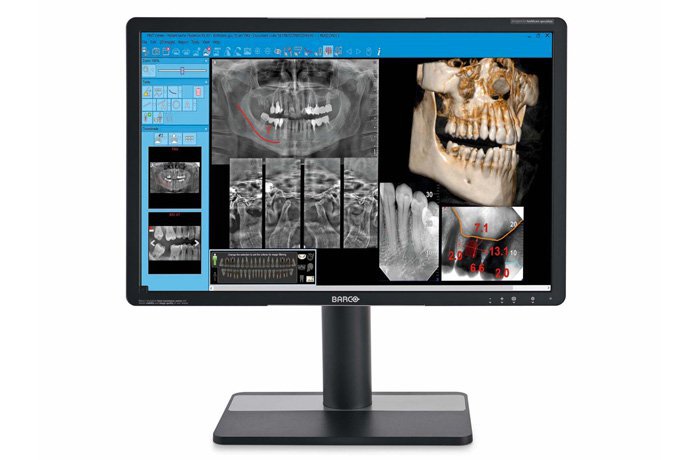

NNT. ПЕРЕДОВЫЕ ФУНКЦИИ ПРОГРАММНОГО ОБЕСПЕЧЕНИЯ

Обширные возможности передачи и обработки с оптимальной платформой визуализации.

Программное обеспечение NewTom NNT предлагает все функции, необходимые для выполнения, обработки, вывода на экран и передачи 2D и 3D результатов обследования. NNT также предоставляет различные режимы и функции приложения, специально предназначенные, чтобы планировать лучшее лечение в области имплантологии, эндодонтии, пародонтологии и рентгенографии, а также в челюстно-лицевой хирургии.